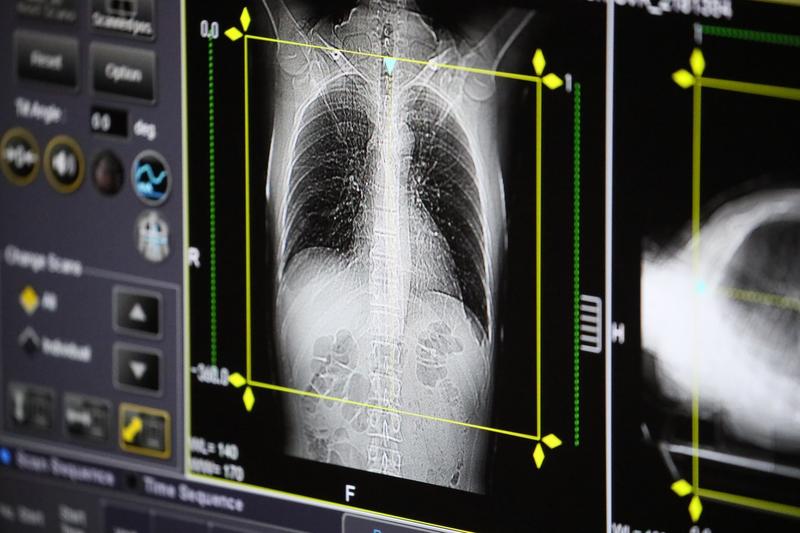

„Este extrem de important să ne îndreptăm căutările sau direcţia de căutare către programe de screening, să îi facem să înţeleagă că orice persoană care fumează de mai mult de 20 de ani, un pachet de ţigări pe zi, trebuie la peste 20 de ani, şi mai ales dacă are mai mult de 55 de ani, să îşi facă un examen CT de torace. În funcţie de rezultat, conduita este variată. Examinările se fac repetat, o lungă perioadă de timp, dar există o condiţie impusă de statele care susţin prin programe de sănătate astfel de programe de screening şi anume abandonarea fumatului”, a mai declarat Mahler.